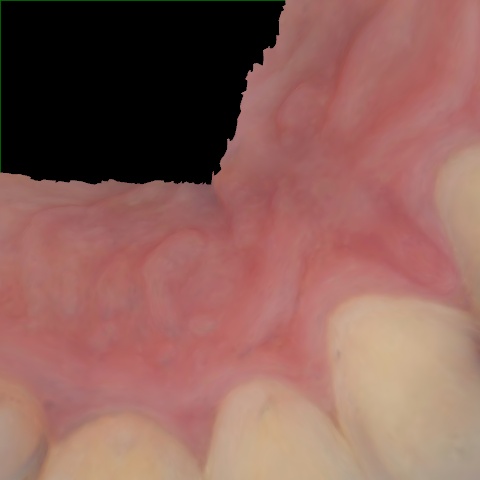

Annotated as "Good"